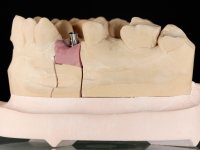

A CT scan was performed to evaluate the available bone heritage and to choose the type and size of implant to be placed. An impression of both jaws was made in alginate, as well as intermaxillary recording for laboratory work on a provisional prosthesis. The provisional prosthesis was made by including a metal wire in a prosthetic tooth adapted to the edentulous space. The root was carefully removed and the implant was placed in the tooth socket corresponding to tooth 1.4. The remaining space between the walls of the alveolus and the implant was filled with regenerative material and then sutured. The prosthesis was previously adapted to the postoperative zone and was then bonded to adjacent teeth. Teflon was used to promote the best possible insulation. Bonding was done using photopolymerizable composite resin using the palatine and inter-proximal walls of the adjacent teeth. After 10 days, the suture was removed and one month later osseointegration was confirmed. Exposure of the implant and placement of the healing screw was performed after 10 weeks. The cervical portion of the provisional tooth had to be reduced to accommodate the healing screw. Stabilized peri-implant soft tissues were impressed using open tray technique with soft and regular consistency putty silicon. In the laboratory the work model was made, along with the choice of pre-fabricated components for the confection of a metal-ceramic crown screwed to the implant with the brand’s interface. Removal of the provisional bridge was done with great care not to touch the interproximal surfaces of the teeth adjacent to the edentulous space. The crown was screwed to the implant, and after imaging, the seating was given the final tightening with 35N of torque. The screw access hole was filled with Teflon and closed with composite resin. The patient manifested satisfaction with the aesthetic and functional rehabilitation achieved.